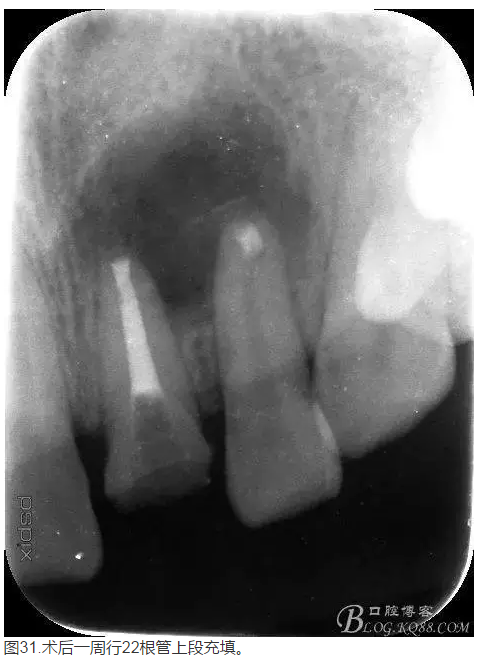

轉:張東星 愛齒-KQ88口腔醫(yī)學